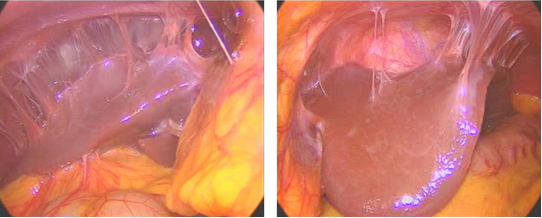

衣原体感染导致盆腔广泛粘连

A.肠管、大网膜与子宫后方、右附件广泛粘连形成包块;B.右附件区包块来自右侧卵巢和输卵管,与周围组织粘连。